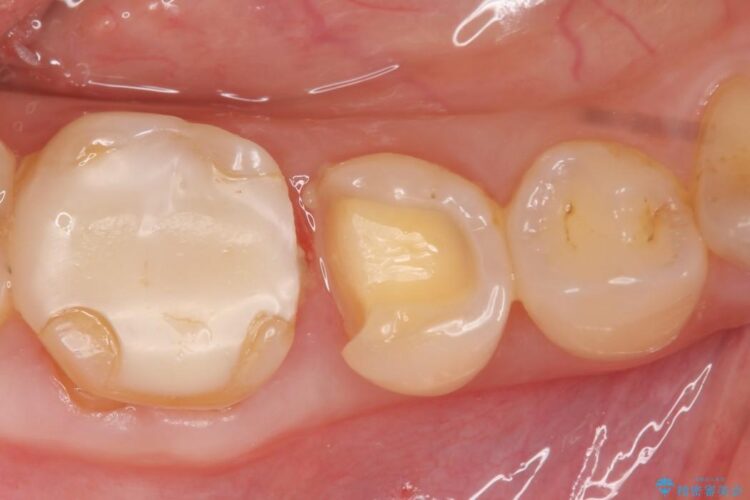

ぱっと見ただけでは特に問題ないように見えますが、レントゲンをよく確認すると詰め物と歯の間に隙間がはっきりと確認ができます。

適合不良であるインレーを放置するリスクを患者様へ説明してご納得いただいた上で、オールセラミックインレーで治療を行うこととしました。

隙間が発生しているインレー(詰め物)